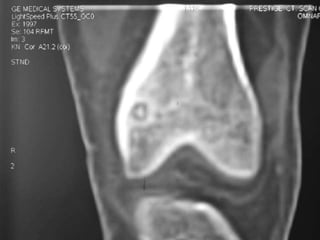

Osteoid Osteoma - CT

• CT is more accurate than MRI.

• CT helped in confirming the diagnosis of

osteoid osteoma in 74% of cases.

• Szendroi et al reported accuracies of about

66% in the diagnosis of intra-articular lesions

and 90% in extra-articular lesions.

• To date, CT scanning is the primary

investigational tool for the definitive diagnosis

of osteoid osteoma.

• A CT guided needle was passed to localize the

lesion.

• Through an anterior "Hernia" approach the

lesion was approached and excised.

• The Follow-up CT Scanning done to reveal

complete removal of lesion.

• A biopsy confirmed it later.

Osteoid Osteoma -CT • CT is more accurate than MRI. • CT helped in confirming the diagnosis of osteoid osteoma in 74% of cases. • Szendroi et al reported accuracies of about 66% in the diagnosis of intra-articular lesions and 90% in extra-articular lesions. • To date, CT scanning is the primary investigational tool for the definitive diagnosis of osteoid osteoma.

• A CTguided needle was passed to localize the lesion. • Through an anterior "Hernia" approach the lesion was approached and excised. • The Follow-up CT Scanning done to reveal complete removal of lesion. • A biopsy confirmed it later.